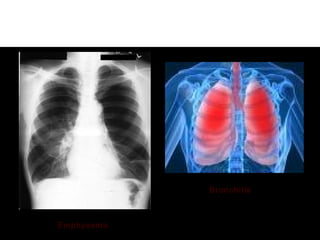

4-X-ray to differentiate between two4-X-ray to differentiate between two

diseases.diseases.

Emphysema

Bronchitis